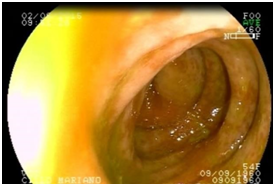

A complete colonoscopy with previous mechanical bowel preparation was performed. The findings include segmental erythema and areas with pale mucosa from the splenic flexure to the rectosigmoideal junction, with rectal spare. Petechial hemorrhages, haustrations edema and fibrin were also described. Biopsy specimens were obtained.

Histologic examination showed epithelium erosion, mucosal and sub mucosal hemorrhage, atrophic crypts and a decrease in the number of caliciform cells. These findings were consistent with ischemic colitis. Conservative treatment was established, with the suppression of the ergotamine suppositories. The patient was discharged 48 hours after admission. No recurrent symptoms were reported. A colonoscopy was performed 6 months after the diagnosis, which showed remission of endoscopic findings (Figure 2).

Figure 2 Colonoscopy:Ischemic colitis.